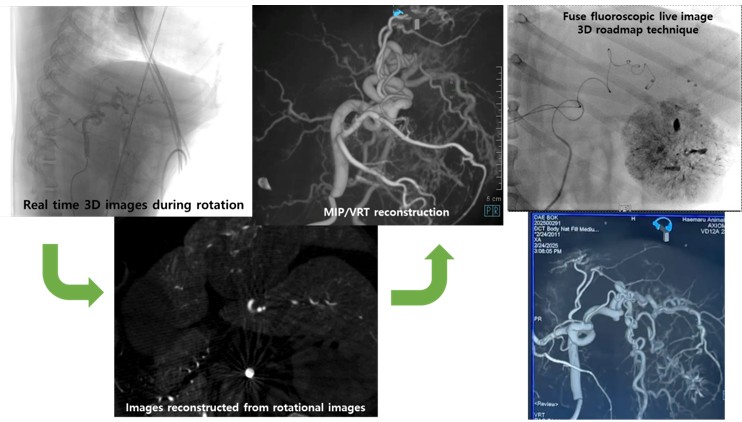

이번 발표는 해마루동물병원이 지난 2024년 12월 전 세계 동물병원 최초로 도입한 독일 지멘스사의 3차원 혈관조영장비인 ‘아티스큐 씰링(Siemens Artis Q Ceiling)’을 이용해 진행한 간암색전술 18건에 대해 회고 분석한 결과를 바탕으로 이루어졌다.

전성훈 센터장은 발표에서 “3차원 혈관조영술을 이용할 경우 간암으로 공급되는 영양동맥을 보다 정확하게 파악할 수 있고, 간 내에 위치하는 영양동맥뿐만 아니라 간 외에서 공급되는 영양동맥(collateral/extraphepatic feeding artery)까지 직접 확인할 수 있어 더 세밀하고 정확한 치료가 가능하다”고 설명했다.

특히 이번 회고 분석에 포함된 18마리 환자 중 7마리에서는 간 외에서 공급되는 영양동맥이 확인됐으며, 그중 3마리는 기존 CT 영상에서 확인되지 않았던 혈관이 3차원 영상으로 파악되어 추가 치료가 이루어졌다. 이를 통해 색전술의 효과는 더 증대되고, 다른 정상적인 혈관으로 색전 물질이 새어나가 발생할 수 있는 비특이적 색전 부작용(non-target embolization)도 최소화했다.